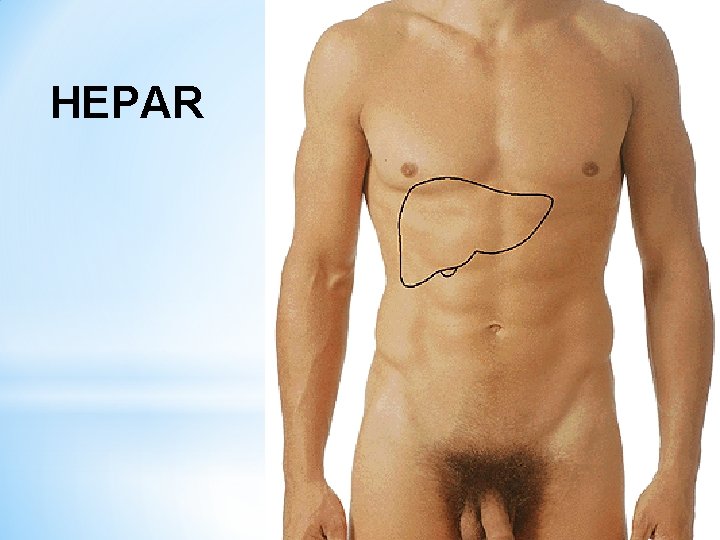

HEPAR